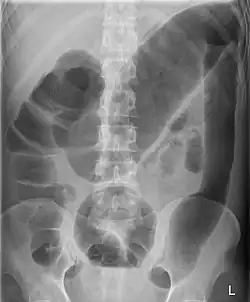

Toxic megacolon associated with ulcerative colitis. | |

Toxic megacolon

Toxic megacolon is mainly seen in ulcerative colitis and pseudomembranous colitis, two chronic inflammations of the colon (and occasionally, in the other type of inflammatory bowel disease, Crohn's disease). Its mechanism is incompletely understood. It is probably due to excessive production of nitric oxide, at least in ulcerative colitis. The prevalence is about the same for both sexes.